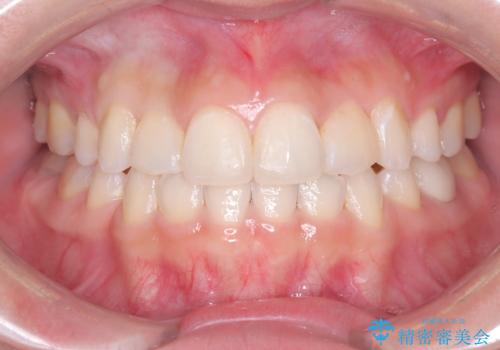

八重歯と正中のズレを解消!目立ちにくいワイヤー矯正で美しい歯並びへ

担当医 河口智英